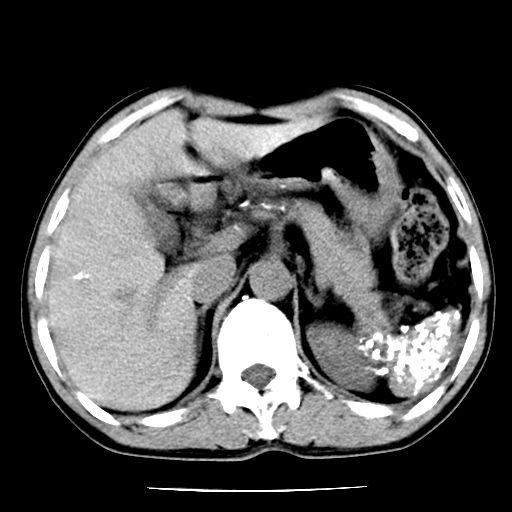

男,59岁,“结核性胸膜炎”30余年,胸部经常疼痛,多次x检查提示“肺部”炎症。腹部疼痛5日,b超提示:“肝内短管结石,余显示不清,建议进一步检查。”

两肺结核并右侧胸腔积液;脾脏、腹腔及腹膜后淋巴结结核[陈旧性];肝内胆管结石

胸部腹部都是结核(双肺。纵隔淋巴结,肝脏,脾脏,肠系膜)

两肺结核并右侧胸腔积液;脾脏、腹腔及腹膜后淋巴结结核[陈旧性];肝内胆管结石。直肠息肉?